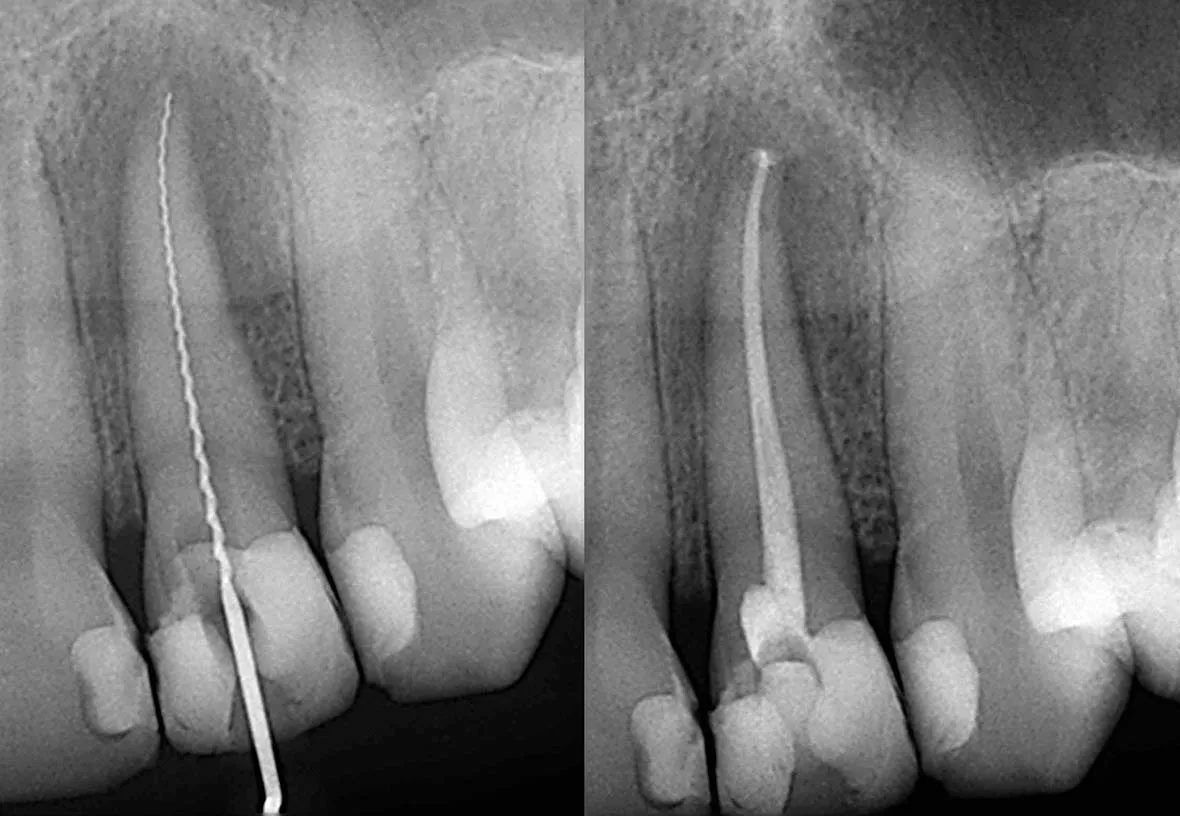

What to Expect During Root Canal Therapy

Root canal treatment involves the removal of the soft inner tissue of the tooth, also called the pulp. Your dentist will drill a tiny hole in the affected tooth and remove the pulp using special tools. After the pulp is removed, your dentist will clean the inside of the tooth to prevent further infection, fill the tooth with material, and seal the hole with a filling. After the procedure, your dentist will restore the tooth with a temporary dental crown while a permanent crown is being made.